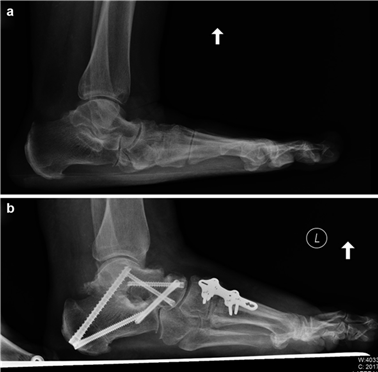

Weight-bearing anteroposterior (AP), lateral, and sesamoid axial radiographs are mandatory. On the AP view, the surgeon measures the Hallux Valgus Angle (HVA, normal < 15°), the Intermetatarsal Angle (IMA, normal < 9°), and the Distal Metatarsal Articular Angle (DMAA). The lateral view is scrutinized for Meary's angle (talo-first metatarsal angle) to identify midfoot collapse, as well as the presence of dorsal osteophytes indicative of hallux rigidus. The sesamoid axial view is critical for assessing the degree of sesamoid subluxation and the integrity of the crista.

Image

The Lapidus Arthrodesis (First TMT Fusion)

For severe deformities or hypermobility, the Lapidus procedure provides robust stabilization of the medial column. A dorsal or medial incision is utilized over the first TMT joint. The extensor hallucis longus (EHL) is retracted dorsally, and the tibialis anterior tendon is identified and protected at its insertion on the medial cuneiform and first metatarsal base. The TMT joint capsule is incised, and the joint is thoroughly debrided of all articular cartilage using a combination of osteotomes, curettes, and a high-speed burr.

To achieve multiplanar correction, the surgeon must address the sagittal, coronal, and transverse planes. The first metatarsal is plantarflexed to restore the longitudinal arch, rotated out of pronation to realign the sesamoids, and translated laterally to close the IMA. Subchondral drilling or feathering is performed to optimize the biological environment for fusion. Fixation is traditionally achieved with two or three crossed solid or cannulated screws (typically 3.5mm or 4.0mm). Recently, plantar or medial locking plates have gained immense popularity due to their superior biomechanical construct, allowing for earlier weight-bearing. Bone graft or orthobiologics may be packed into the arthrodesis site to stimulate osteogenesis.

First MTP Arthrodesis

In cases of end-stage hallux rigidus, first MTP arthrodesis yields excellent, predictable outcomes. A dorsal longitudinal incision is made just medial to the EHL tendon. The joint is exposed, and aggressive cheilectomy is performed to remove all dorsal, medial, and lateral osteophytes. The remaining articular cartilage on the metatarsal head and the base of the proximal phalanx is resected using cup-and-cone reamers, which allow for infinite adjustment of the joint position prior to fixation.

Positioning of the fusion is the most critical step of the operation. The hallux must be positioned in 10-15 degrees of valgus, 15-20 degrees of dorsiflexion relative to the first metatarsal, and neutral rotation. Excessive dorsiflexion causes shoe impingement, while insufficient dorsiflexion leads to vaulting during gait and interphalangeal joint arthritis. Fixation is most reliably achieved using a pre-contoured dorsal locking plate combined with a lag screw crossing the fusion interface.